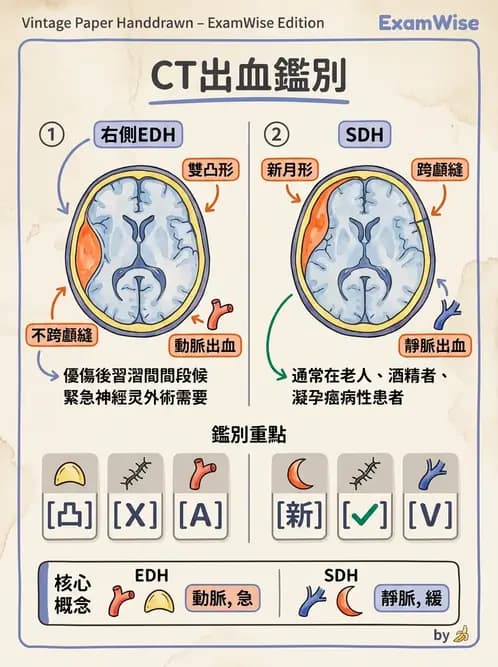

影像特徵判讀:

- 雙凸形(biconvex)高密度病灶 → 硬腦膜上腔出血(epidural hematoma, EDH)的典型 CT 特徵

- 位置在右側半球,位於硬腦膜與顱骨之間的硬腦膜外(上)腔

- 病灶不跨越顱縫,符合 EDH(硬腦膜與顱縫緊密黏附,限制出血範圍)

→ 結論:右側硬腦膜上腔(右側 epidural hematoma)出血,即選項 (C)